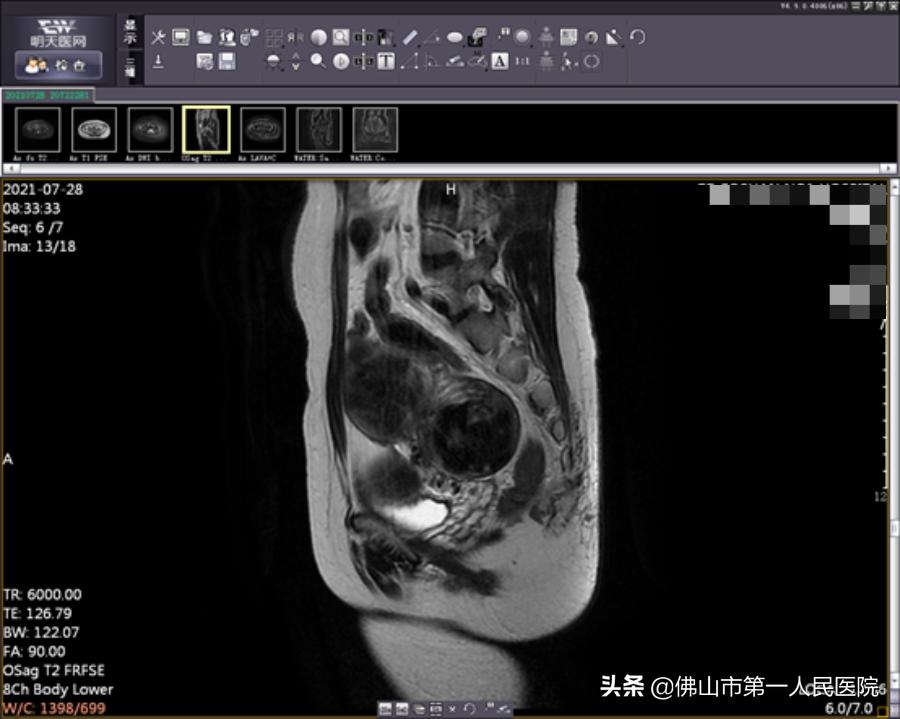

术前图像

2年前,42岁的陆女士因尿频尿急和不孕多年到医院就诊,经磁共振检查发现,子宫肌瘤多达近20个。辗转多家医院均建议手术治疗切除,但术后肌瘤复发几率高,且子宫会有疤痕,妊娠可能出现子宫破裂等风险。

经充分检查和术前评估,陆女士符合“海扶刀”治疗指征。由于陆女士子宫肌瘤分布于于肌壁间、黏膜下和浆膜下,数量较多,大小不一,我院海扶中心潘智茵副主任及其团队结合多年“海扶刀”治疗经验,制定了宫腔镜检查联合“海扶刀”手术的治疗方案。

2021年7月,医生为陆女士行宫腔镜检查,子宫内膜未见明显异常,粘膜下肌瘤向宫腔凸起小于二分之一,大于二分之一位于肌壁间。宫腔镜检查术后1天患者无明显阴道流血,遂行海扶刀手术。